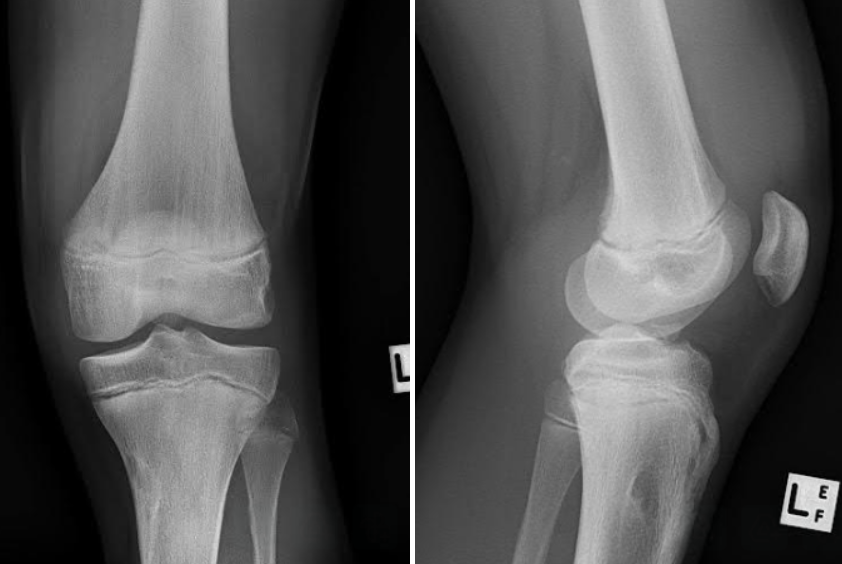

Jump, Land, and Tear

A 32-year-old male patient presented to the emergency department due to left knee pain. He was playing basketball when he came down from a vertical jump onto his left leg. He stated his kneecap appeared to be displaced laterally. On examination, patient had decreased range of motion of the left knee, tenderness on palpation of the lateral and medial aspect of the knee, and he was unable to extend his knee.